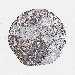

LIVER CANCER - Protein expressioni

A mouse-over function shows sample information and annotation data. Click on an image to view it in a full screen mode. Samples can be filtered based on level of antibody staining by selecting one or several of the following categories: high, medium, low and not detected. The assay and annotation is described here.

Note that samples used for immunohistochemistry by the Human Protein Atlas do not correspond to samples in the TCGA dataset.

Antibody stainingi

Antibody staining in the annotated cell types in the current human tissue is reported as not detected, low, medium, or high, based on conventional immunohistochemistry profiling in selected tissues. This score is based on the combination of the staining intensity and fraction of stained cells.

Each image is clickable and will lead to virtual microscopy that enables deeper exploration of all samples and also displays staining intensity scores, fraction scores and subcellular localization as well as patient and tissue information for each sample.

Antibody HPA039687

Antibody HPA040036

Staining

High

Medium

Low

Not detected

Intensity

Strong

Moderate

Weak

Negative

Quantity

>75%

75%-25%

<25%

None

Location

Nuclear

Cytoplasmic/membranous

Cytoplasmic/membranous,nuclear

Cholangiocarcinoma

Carcinoma, Hepatocellular, NOS